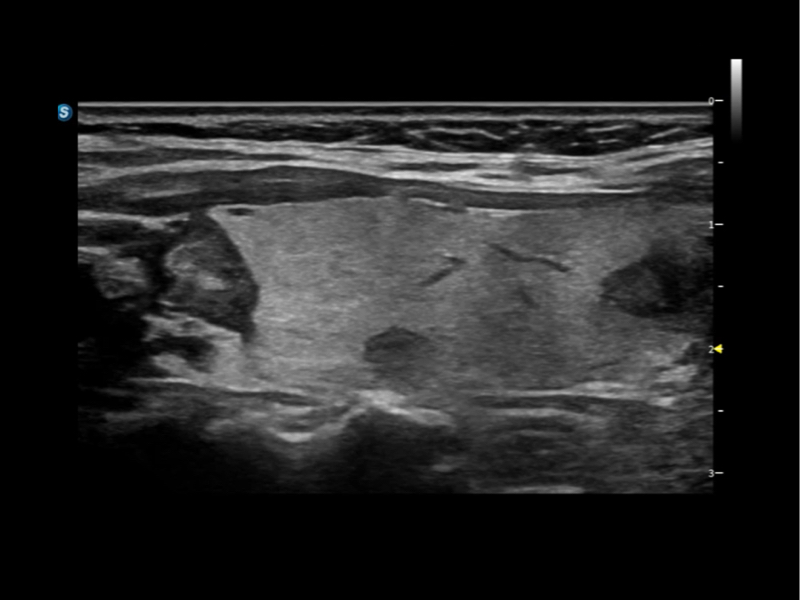

通過創(chuàng)新的Matrix E自適應(yīng)濾波算法,能有效濾除軟組織和噪聲信號(hào),最大限度保留超低速微細(xì)血流的信號(hào);結(jié)合超長(zhǎng)時(shí)間域算法,極大提升細(xì)微血流的敏感性和空間分辨率,更真實(shí)的反應(yīng)組織、包塊的血流灌注情況。